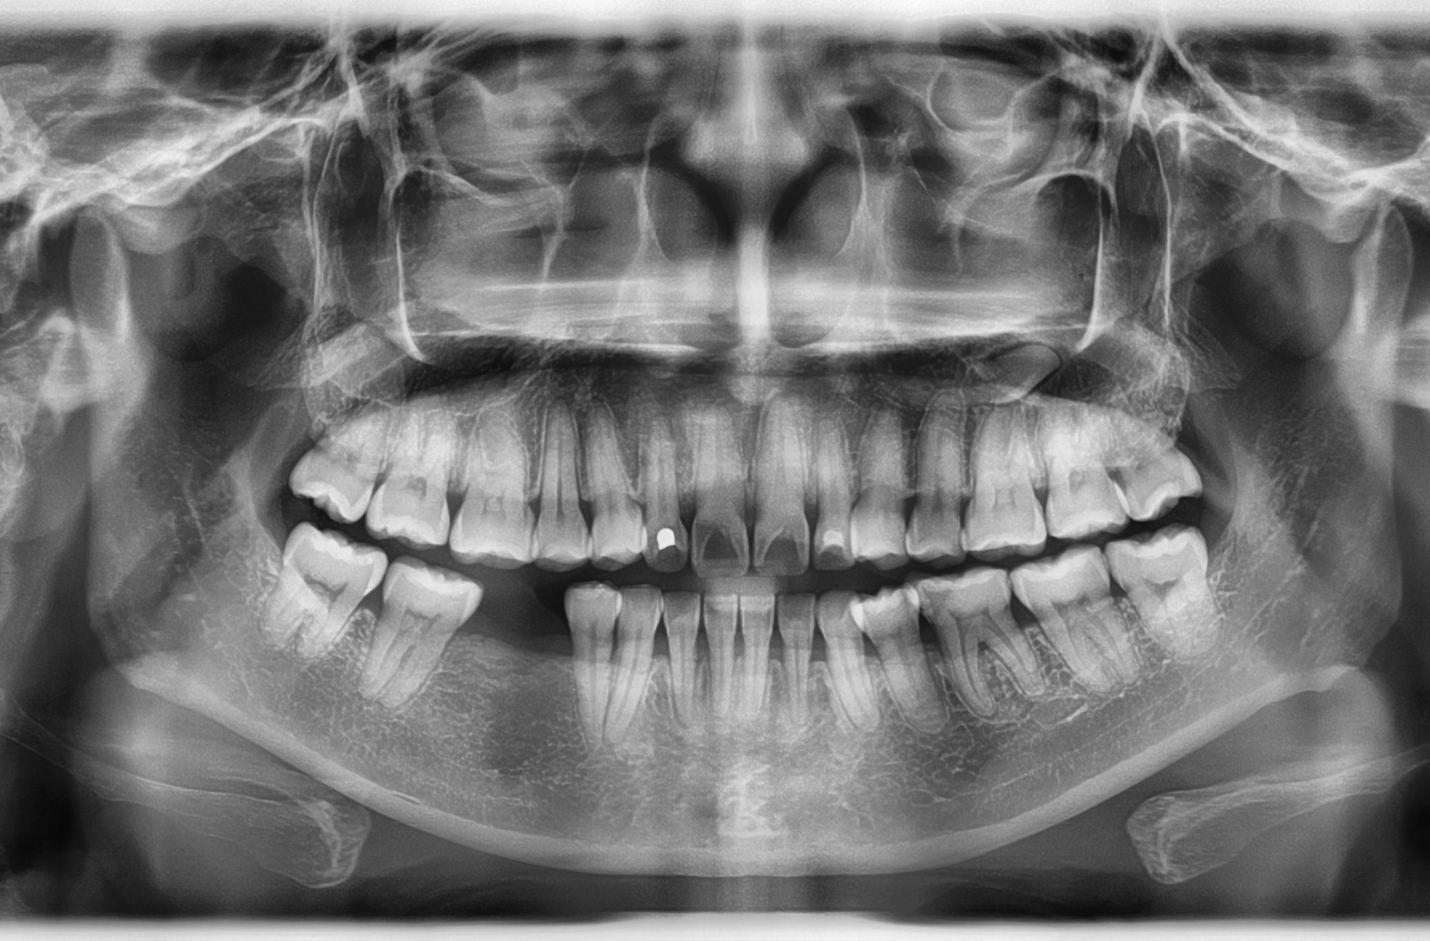

When a tooth is lost, that stimulation stops. Without it, the surrounding bone begins to resorb, or shrink, as the body redirects minerals elsewhere. Over time, this can cause the jawbone to thin and the gum line to recede, altering facial contours and creating a prematurely aged appearance.

Dental implants replicate the structure of natural tooth roots. Each implant consists of a small titanium post surgically placed into the jawbone. Over the next few months, the bone grows and fuses around the post in a process called osseointegration.

This fusion allows the implant to function just like a natural root, delivering the same kind of mechanical stimulation needed to maintain bone density. As a result, implants effectively halt bone loss and help preserve the strength and volume of the jaw.